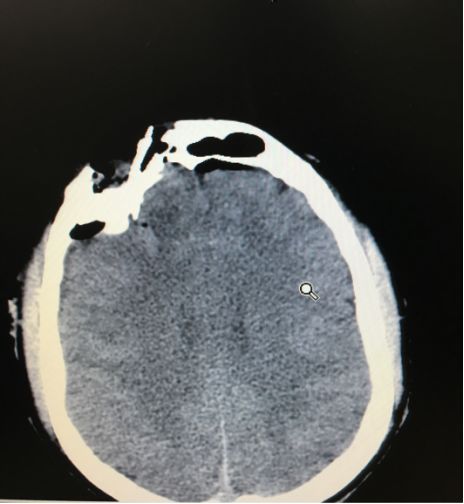

术前CT

![]()